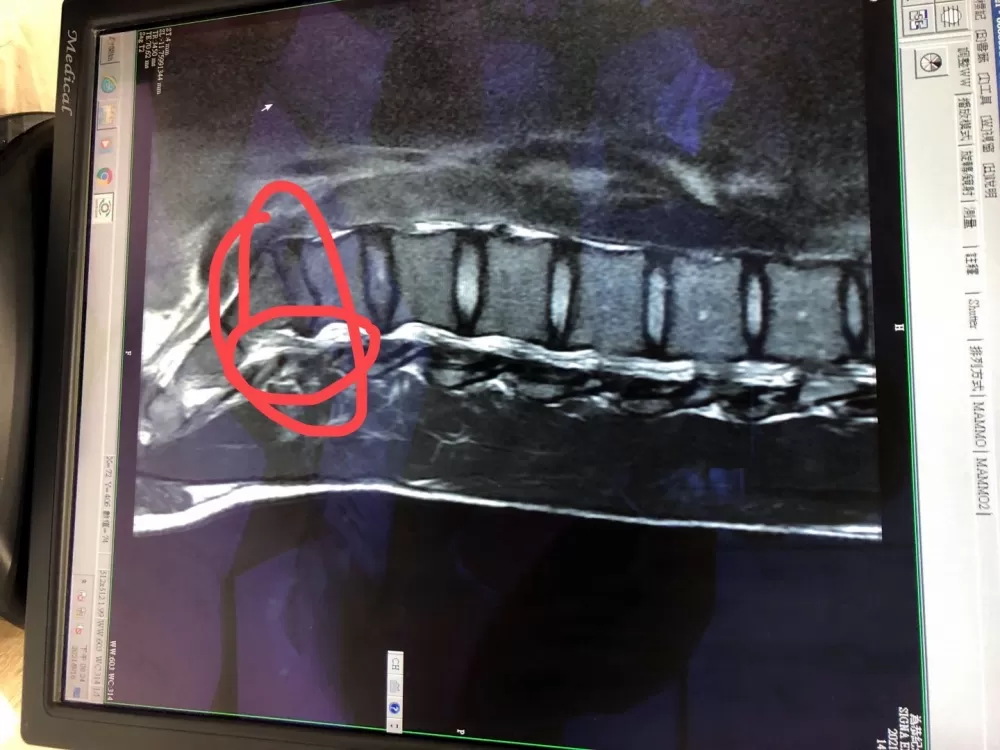

在教練團安排下,康世峰到醫院照了X光和MRI核磁共振後,發現是第四和第五節脊椎壓迫到神經,也就是自由車運動員最常發生的職業病──椎間盤突出。

「整整一週,我無法做任何的訓練,只能勤奮跑醫院和復健診所做治療,盡可能舒緩疼痛,但同時也擔心藥物是否有禁藥成份,很感謝國訓中心給了我們安心的答案,醫生在我第四和第五節脊椎間打了一針,讓我可以安心參加全運。」